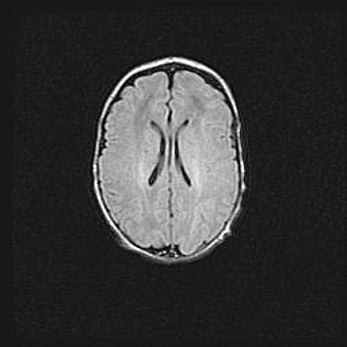

Открытая гидроцефалия.

Возраст: 6 месяцев 15 дней

Вес: 6200 г

Пол: женский

Окружность головы: 41 см

Срок гестации: 38 недель

Гидроцефалия головного мозга у новорожденных – это скопление избыточного количества цереброспинальной жидкости в головном мозге. Ее избыточное скопление в мозге приводит к патологическому расширению желудочков мозга (четырех полостей, расположенных в глубине белого вещества мозга, заполненных цереброспинальной жидкостью и связанных узкими проходами).

Открытый тип гидроцефалии (сообщающаяся) наблюдается тогда, когда нарушен механизм всасывания ликвора в системный кровоток. При этом типе причиной заболевания чаще всего является перенесенные ранее инфекции (например: менингит),  либо же наличие крови в субарахноидальном пространстве.